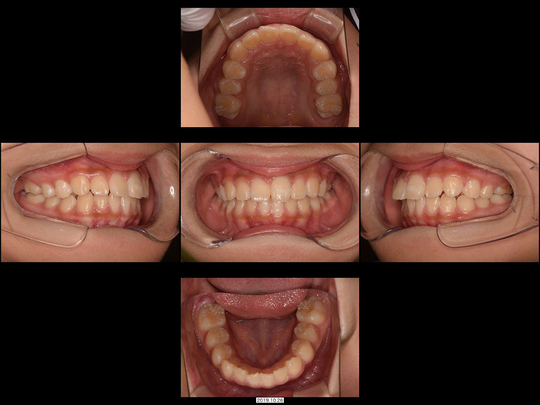

Wさん 開始時8歳 女性

矯正前

前歯がねじれているのを改善したいというご希望でした。「抜歯するしかない」と診断されるような状態です。

固定式の拡大装置を用いて前歯と奥歯の永久歯が生え変わるスペースを作り、正しい歯並びと咬み合わせに誘導(咬合誘導)しました。非抜歯・ワイヤー矯正なしで終了できています。

36か月、36回

462,000円

リスクや副作用:装置に慣れるまでに1週間ほどかかる可能性があります。歯列を広げる過程で少し痛みを感じる可能性があります。装着時に多少しゃべりづらくなる可能性があります(2~3週間ほどで慣れます)。